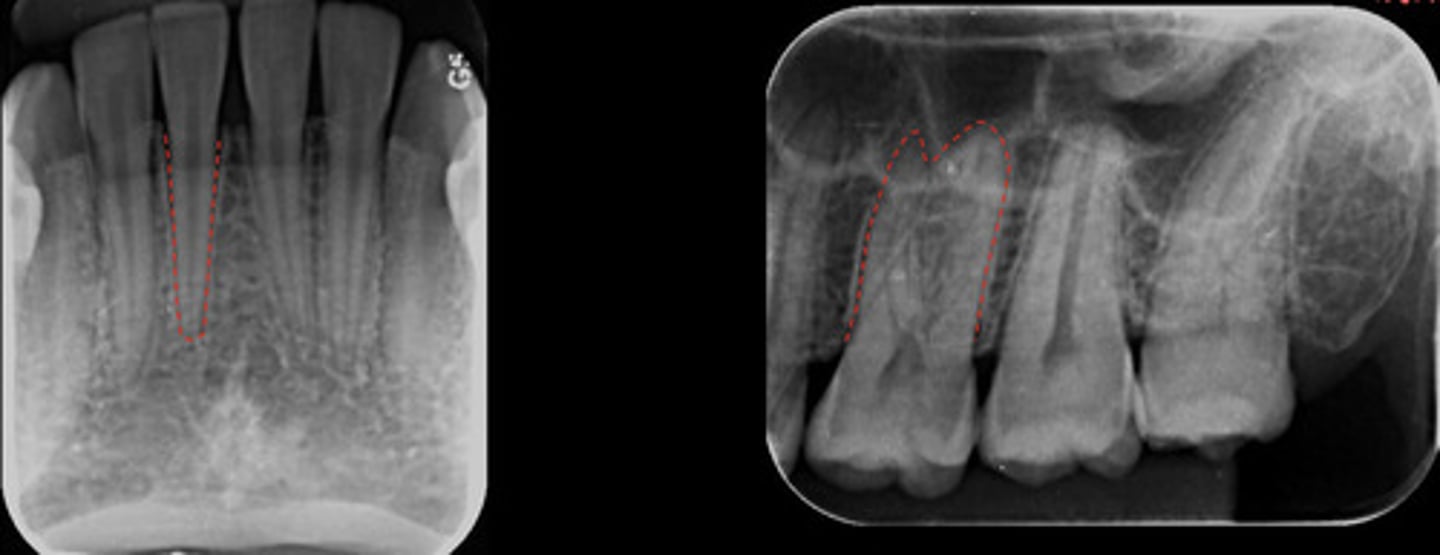

What is the red dotted line representing?

Intermaxillary suture

Incisive foramen